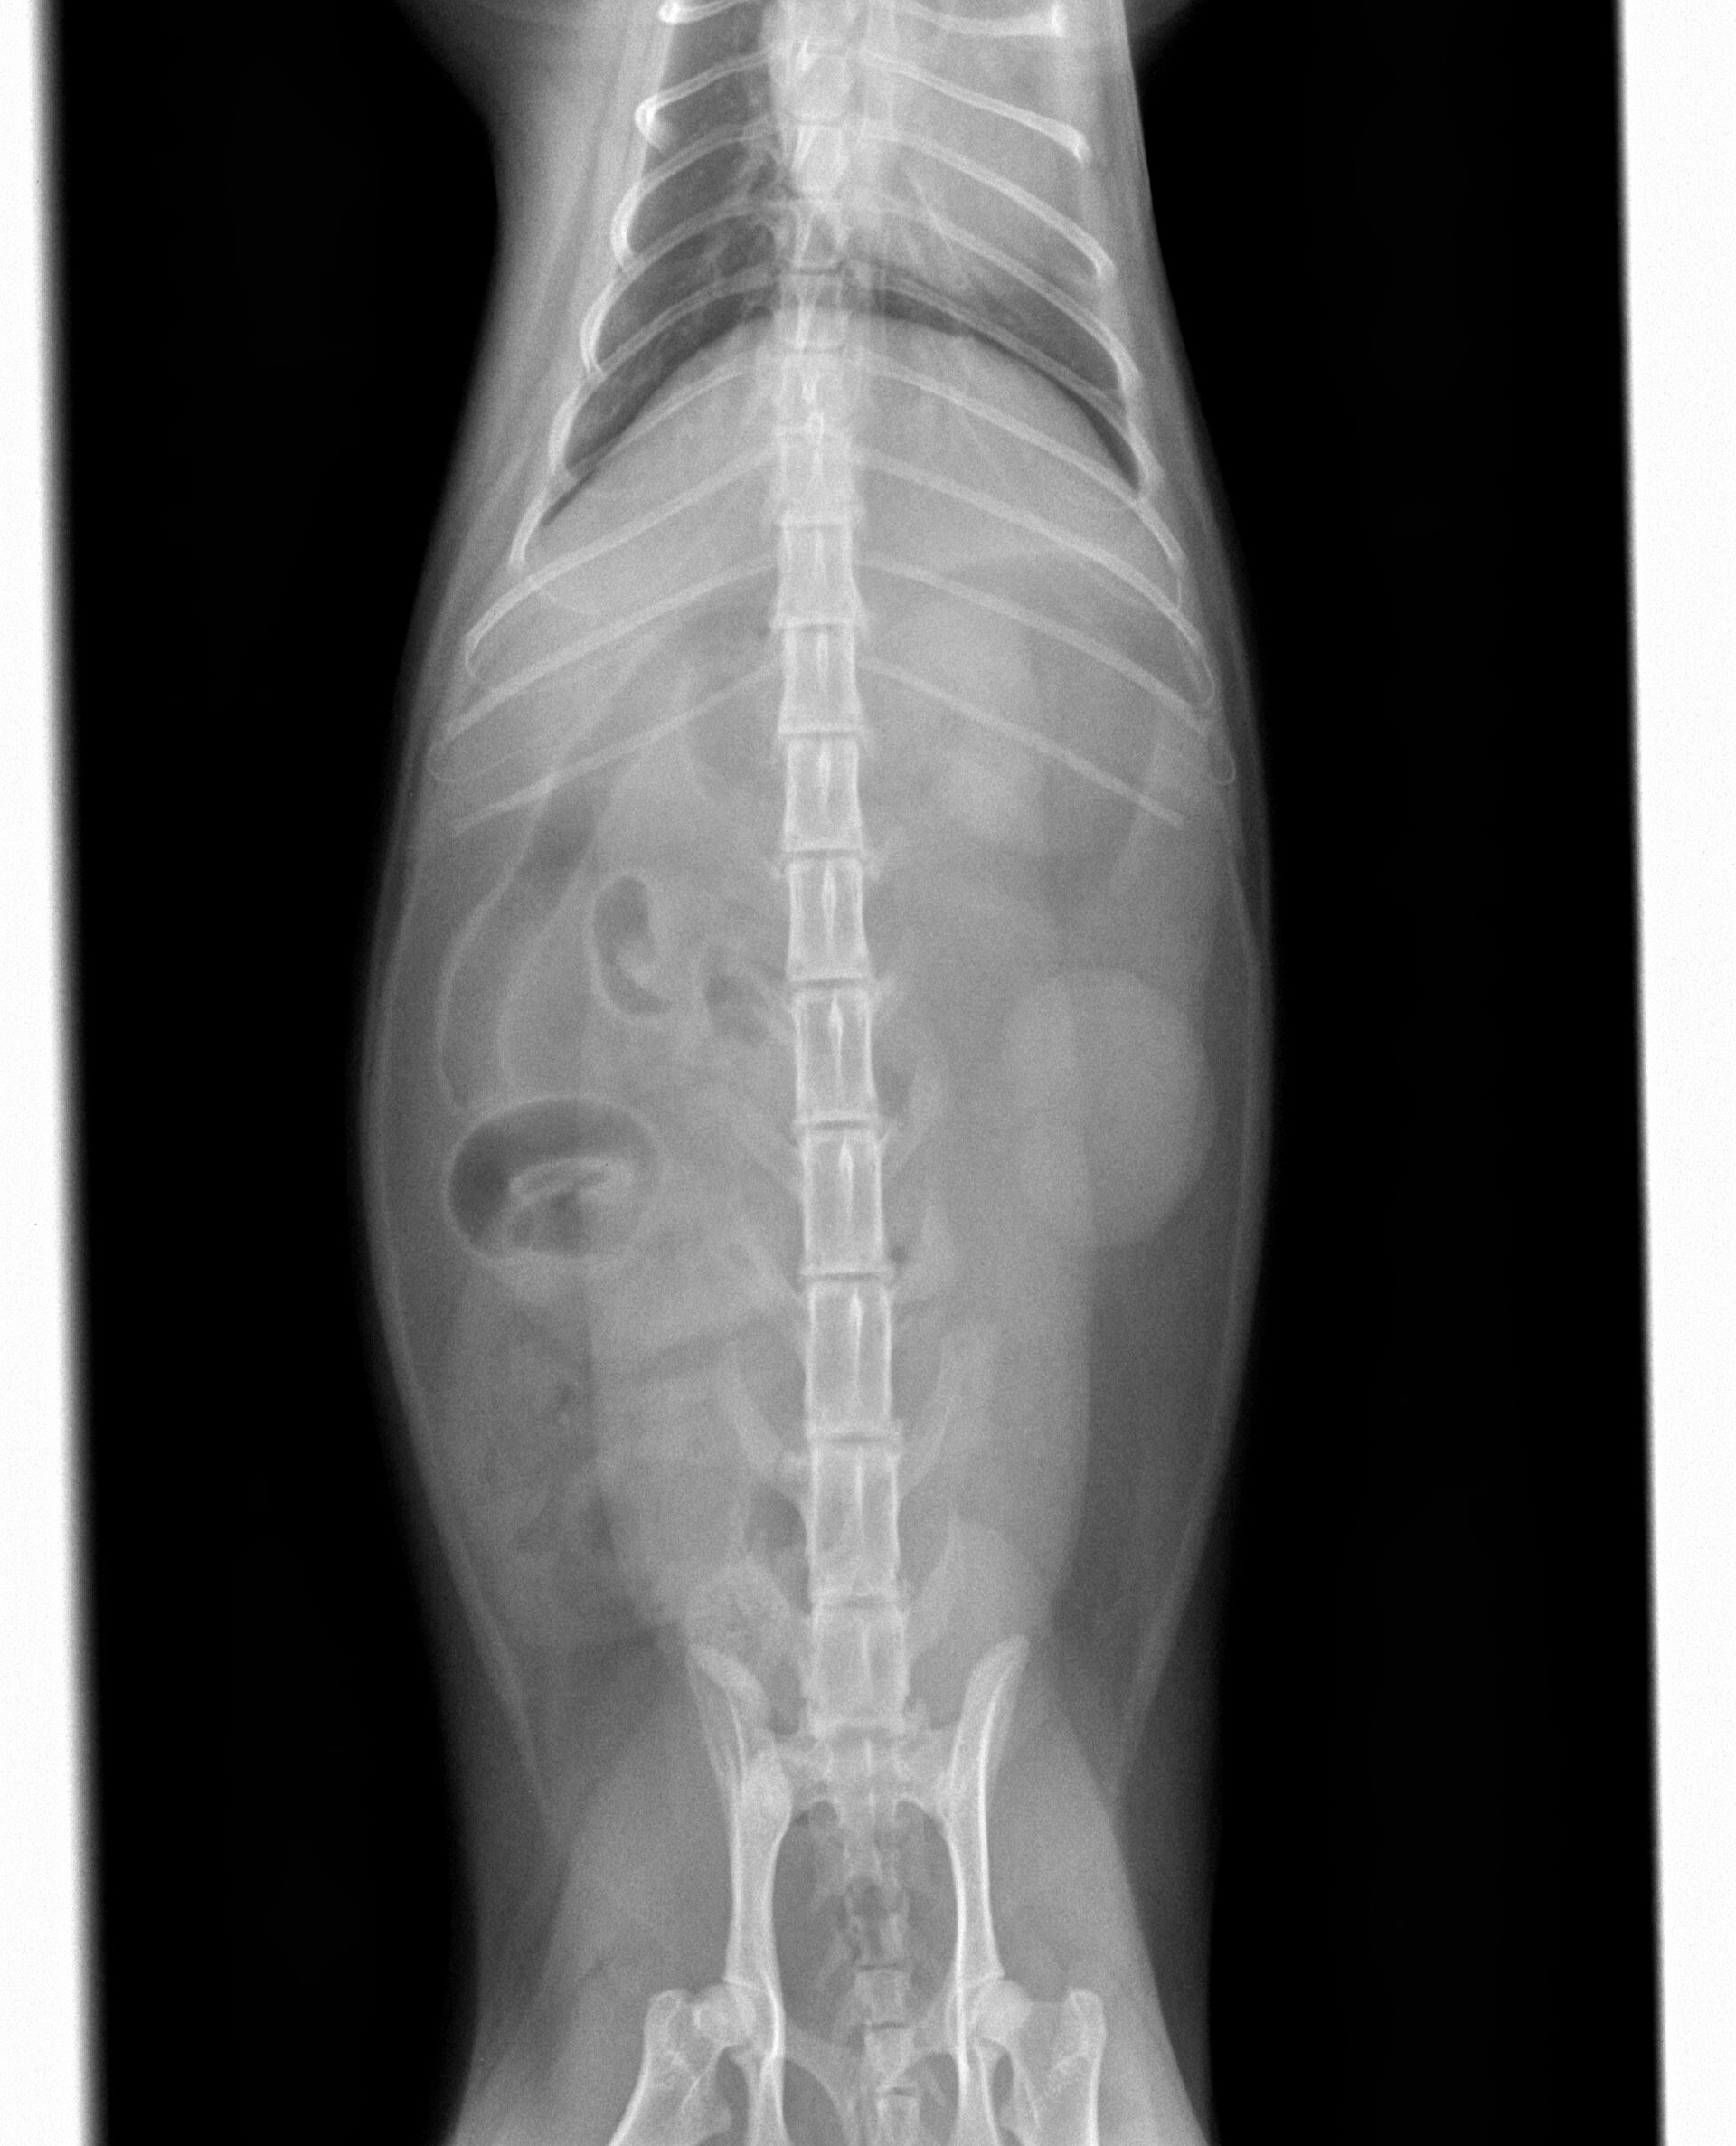

ある日突然食欲がなくなり、定期的に嘔吐するようになったとのことで来院しました。診察したところ、39度の微熱がある以外は脱水もなく、お腹を痛がったり、お腹に異物が触知されるということはありませんでした。また、飼い主さんに確認したところ、色々なものをかんだりすることがあるとのことでしたので、レントゲン撮影を行いました。その結果は特に異常は認められませんでした。